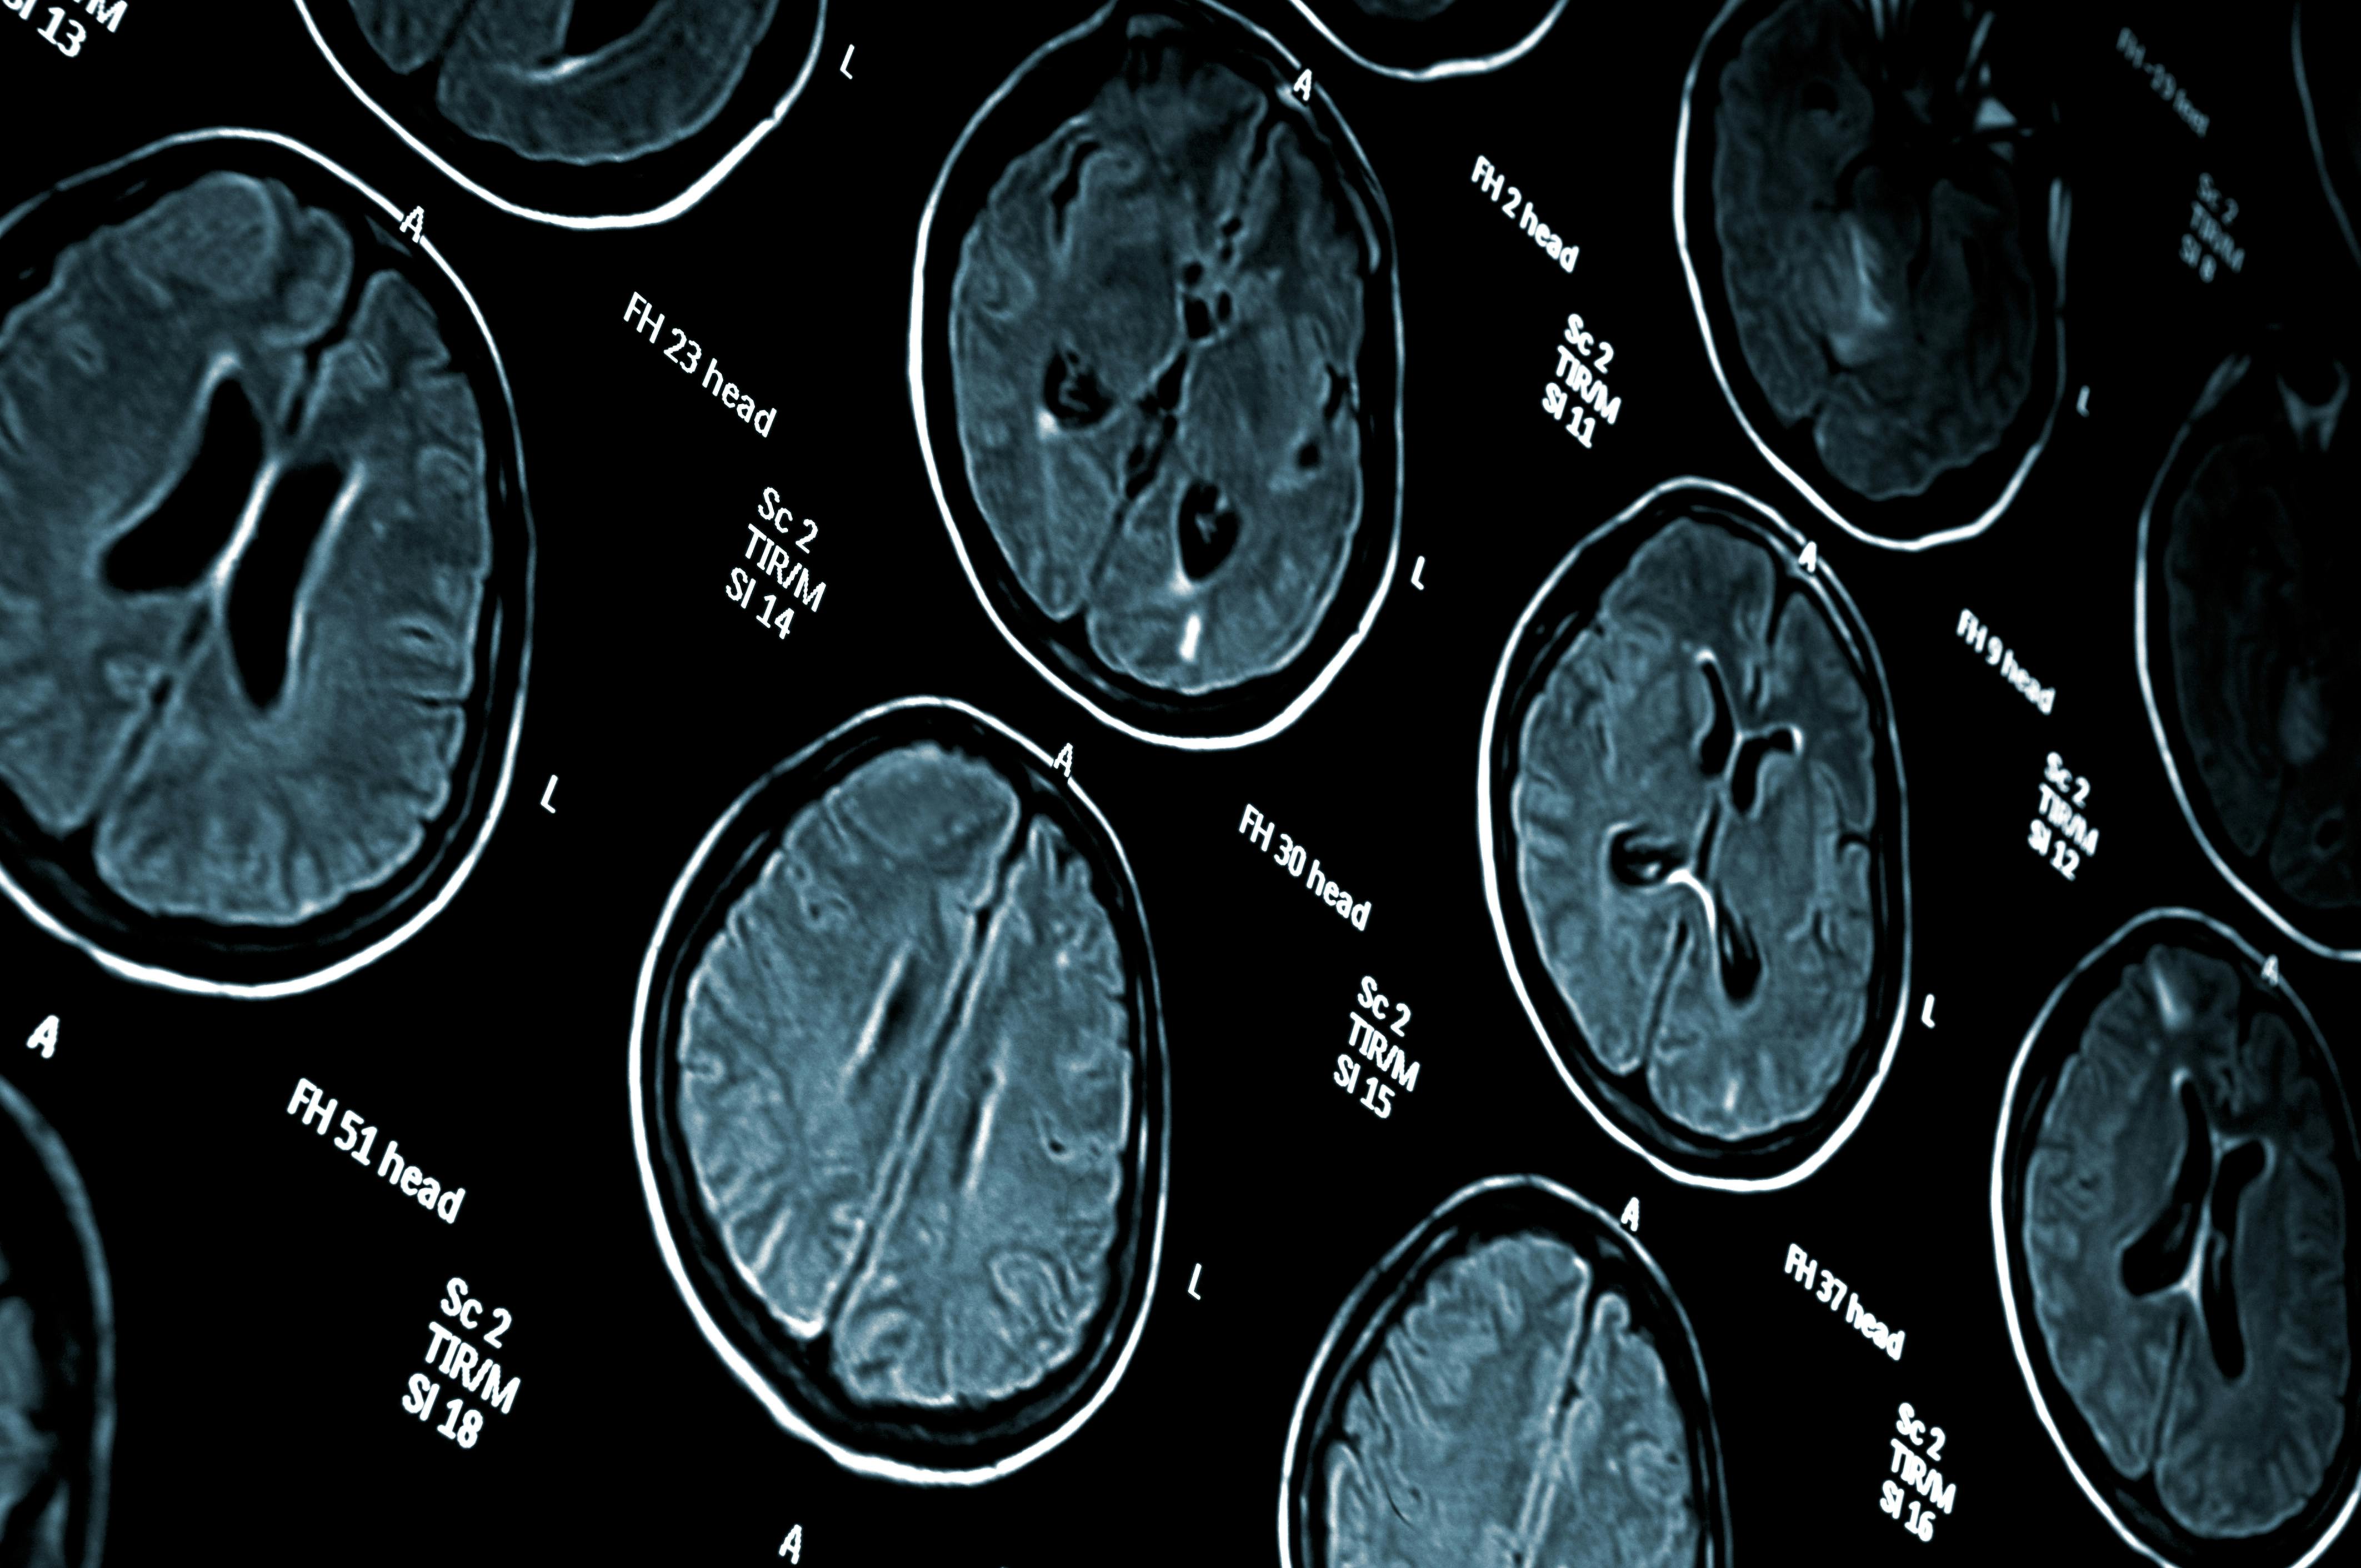

Medical imaging—ideally with MRI—plays an increasingly important role in the diagnostic work-up of cognitive impairment. However, it is unknown how disparities in imaging access may lead to these delays in cognitive impairment diagnoses.